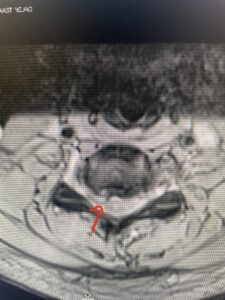

This 36-year-old female who had a long history of neck pain had a history on MRI of a C5-6 bulge. She recently after diving into a pool (not hitting her head on bottom) developed progressive problems with her arms. She had developed spontaneous shocks going down her arms and in the back of her neck. Spontaneous shocks going down the neck and spine is called a Lhermitte’s phenomenon and can occur with spinal cord compression and also with multiple sclerosis. On examination, the patient had long tract weakness of her arms, right greater than left. Her finger extensor weakness was profound on the right. MRI (Fig. 4) of the cervical spine revealed a massive C5-6-disc herniation causing significant cord compression right greater than left with subtle cord signal change. Because of the severe myelopathy, the patient was indicated for surgery. A C5-6 anterior cervical discectomy and fusion was performed (Fig. 5). The patient had a dramatic improvement of her strength in the recovery room.

Fig 4. Axial T2-weighted MRIs demonstrating large C5-6 herniated disc with spinal cord compression (red arrow)